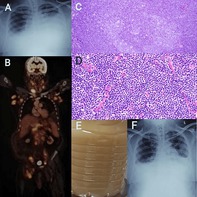

乳糜胸的特点是乳糜积聚在胸膜间隙,是一种罕见但临床意义重大的疾病。这种淋巴液富含从肠道吸收的脂肪,可由各种因素引起,包括创伤、恶性肿瘤和肺结核(TB)。创伤原因,特别是医源性手术,占病例的很大比例,其次是罕见的病因,如恶性肿瘤,如淋巴瘤,以及不太常见的结核病。在前两例中,患者在乳糜胸检查时被诊断为结核病;然而,在第三例中,患者发展为乳糜胸作为套细胞淋巴瘤(MCL)的并发症。2例男性患者,年龄分别为43岁和45岁,表现为呼吸道症状和乳白色胸腔积液(甘油三酯> 180 mg/dL)。在这两例患者中,支气管肺泡灌洗证实为利福平敏感性结核。两例患者均对抗结核治疗和饮食调整有反应。69岁男性,有非霍奇金淋巴瘤病史,乳糜胸(甘油三酯286 mg/dL)和淋巴结病变;影像学和活检证实MCL。他对化疗有反应。这一系列强调了在评估和根据特定病因定制治疗时考虑乳糜胸不常见原因的重要性。

Chylothorax, characterised by the accumulation of chyle in the pleural space, is a rare yet clinically significant condition. This lymphatic fluid, rich in fats absorbed from the intestine, can be caused by various factors including trauma, malignancy, and tuberculosis (TB). Traumatic causes, particularly iatrogenic procedures, account for a significant proportion of cases, followed by rare etiologies like malignancies such as lymphoma, and less commonly, tuberculosis. In the first two cases, the patient was diagnosed with tuberculosis during evaluation for chylothorax; however, in the third case, the patient developed chylothorax as a complication of mantle cell lymphoma (MCL). Two male patients, aged 43 and 45, presented with respiratory symptoms and milky pleural effusions (triglycerides > 180 mg/dL). In both, bronchoalveolar lavage confirmed rifampicin-sensitive TB. Both patients responded to anti-tubercular therapy and dietary modification. A 69-year-old male with a history of non-Hodgkin's lymphoma developed chylothorax (triglycerides 286 mg/dL) and lymphadenopathy; imaging and biopsy confirmed MCL. He responded to chemotherapy. This series underscores the importance of considering uncommon causes of chylothorax during evaluation and tailoring treatment based on specific etiologies.